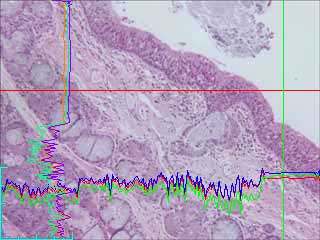

Transmitted light image of an H&E stain lung section. Note the darker band at the left edge, and, to a lesser extent, on the right edge. [image 1]

The dark bands are clearly shown in the line histograms take at the vertical straight line and horizontal strait red lines. The horizontal intensity shows a curvature down on the right, and the left edge has less intensity than the central region, even though the section has no structure that ought to be darker at that edge.

Line histograms of vertical (green) and horizontal (red) cross hairs show curvature due to shading as a result of the unevenness of the illumination.

After shading correction the red cross hair line histograms now does not have the curve down on the right hand edge or the lower levels on the left hand edge. Also the non noisy region of the vertical line histogram (of the green line) is straight.